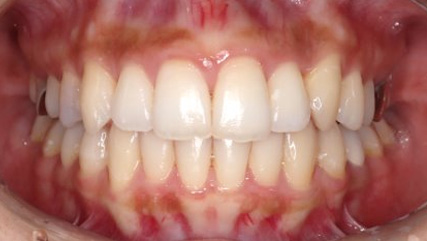

治療前

治療終了前